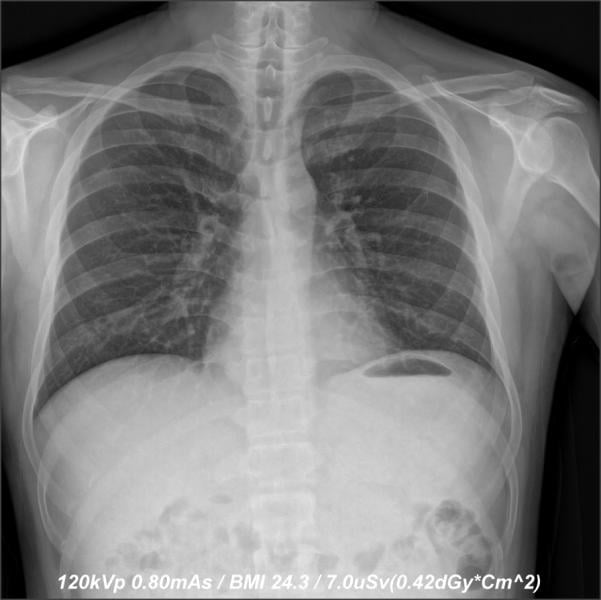

The images (before) depict a 50 percent dose reduction in chest X-ray without compromising

image quality.

When an opportunity to conduct a reduced-dose study with Samsung arose, DeAngelo and his team accepted. The 2017 study was aimed at reducing the radiation dose of adult chest X-rays by 50 percent utilizing Samsung’s GC85A digital radiography (DR) system.

“The goal in radiology, especially in diagnostic radiology, is to produce quality images with the lowest radiation dose possible,” said Hetal Patel, M.D., Greensboro Radiology PA, Chief of Radiology at Cone Health-ARMC. He noted that when applying the new Samsung algorithm, they were able to reduce the dose by 50 percent and maintain the same image quality as previous doses — or in some instances better. This approach could be applied to other areas, he explained, noting, “We are very excited about opening the possibilities for all types of diagnostic radiology.”

During the reduced-dose study, Patel evaluated 10 posterior anterior (PA) chest X-rays. Each X-ray was evaluated under three settings: H++ (sharp), M++ (medium sharpness) and S++ (soft, or similar to computed radiography [CR]). “I felt that the M++ displayed the PA chest best,” concluded Patel. “The overall image quality was excellent in all 10 instances. No X-ray had to be repeated to improve image quality.

“The degree of penetration was excellent, which was best delineated by the improved visualization of the retro-cardiac region on the PA view,” Patel continued. “The remainder of the anatomic structures was also clearly demarcated on all 10 X-rays, [as well as] the boney structures.”

Prior patient X-rays were also used in the study to compare quality. The reduced-dose X-rays were judged to be of either comparable quality or improved quality over the previously captured images. Patel believes the reduced-dose algorithm would be applicable to all types of X-ray exams, and would accomplish many radiologists’ goals of reducing radiation dose for all patients.